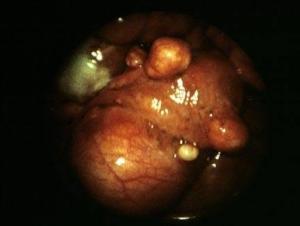

浆膜下子宫肌瘤 肌瘤向子宫浆膜面生长,突起在子宫表面,约占20%。肌瘤表面仅由子宫浆膜层覆盖。当瘤体继续向浆膜面生长,仅有一蒂与子宫肌壁相连,成为带蒂的浆膜下肌瘤,营养由蒂部血管供应。因血供不足易变性、坏死。若蒂部扭转而断裂,肌瘤脱落至腹腔或盆腔,形成游离性肌瘤。

浆膜下肌瘤及肌壁间小肌瘤常无明显月经改变。蒂扭转时出现急性腹痛。肌瘤红色变时,腹痛剧烈且伴发热。下腹坠胀、腰酸背痛常见,且经期加重。可扪及质硬、球状块物与子宫有细蒂相连,活动。